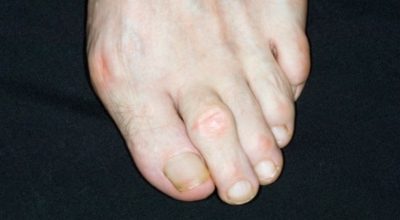

3. 엄지발가락 통증 - 무지외반증

우리에게 잘 알려져 있는 엄지발가락 통증의 원입니다. 선천적 요인으로 인한 발병보다는 하이힐, 뾰족구두, 키높이 깔창과 같이 앞이 좁고 엄지발가락에 자극이 심한 신발 유행으로 후천성 환자가 늘어나고 있습니다. 체중 증가나 류마티스 관절염도 무지외반증의 원인입니다. 엄지발가락이 둘째 발가락으로 휘어지면서 대측으로 회전해서 제1중족 관절이 안쪽으로 돌출되는 무지외반증은 서있거나 걸어 다닐때 신발과 마찰해 통증과 염증이 발생합니다.